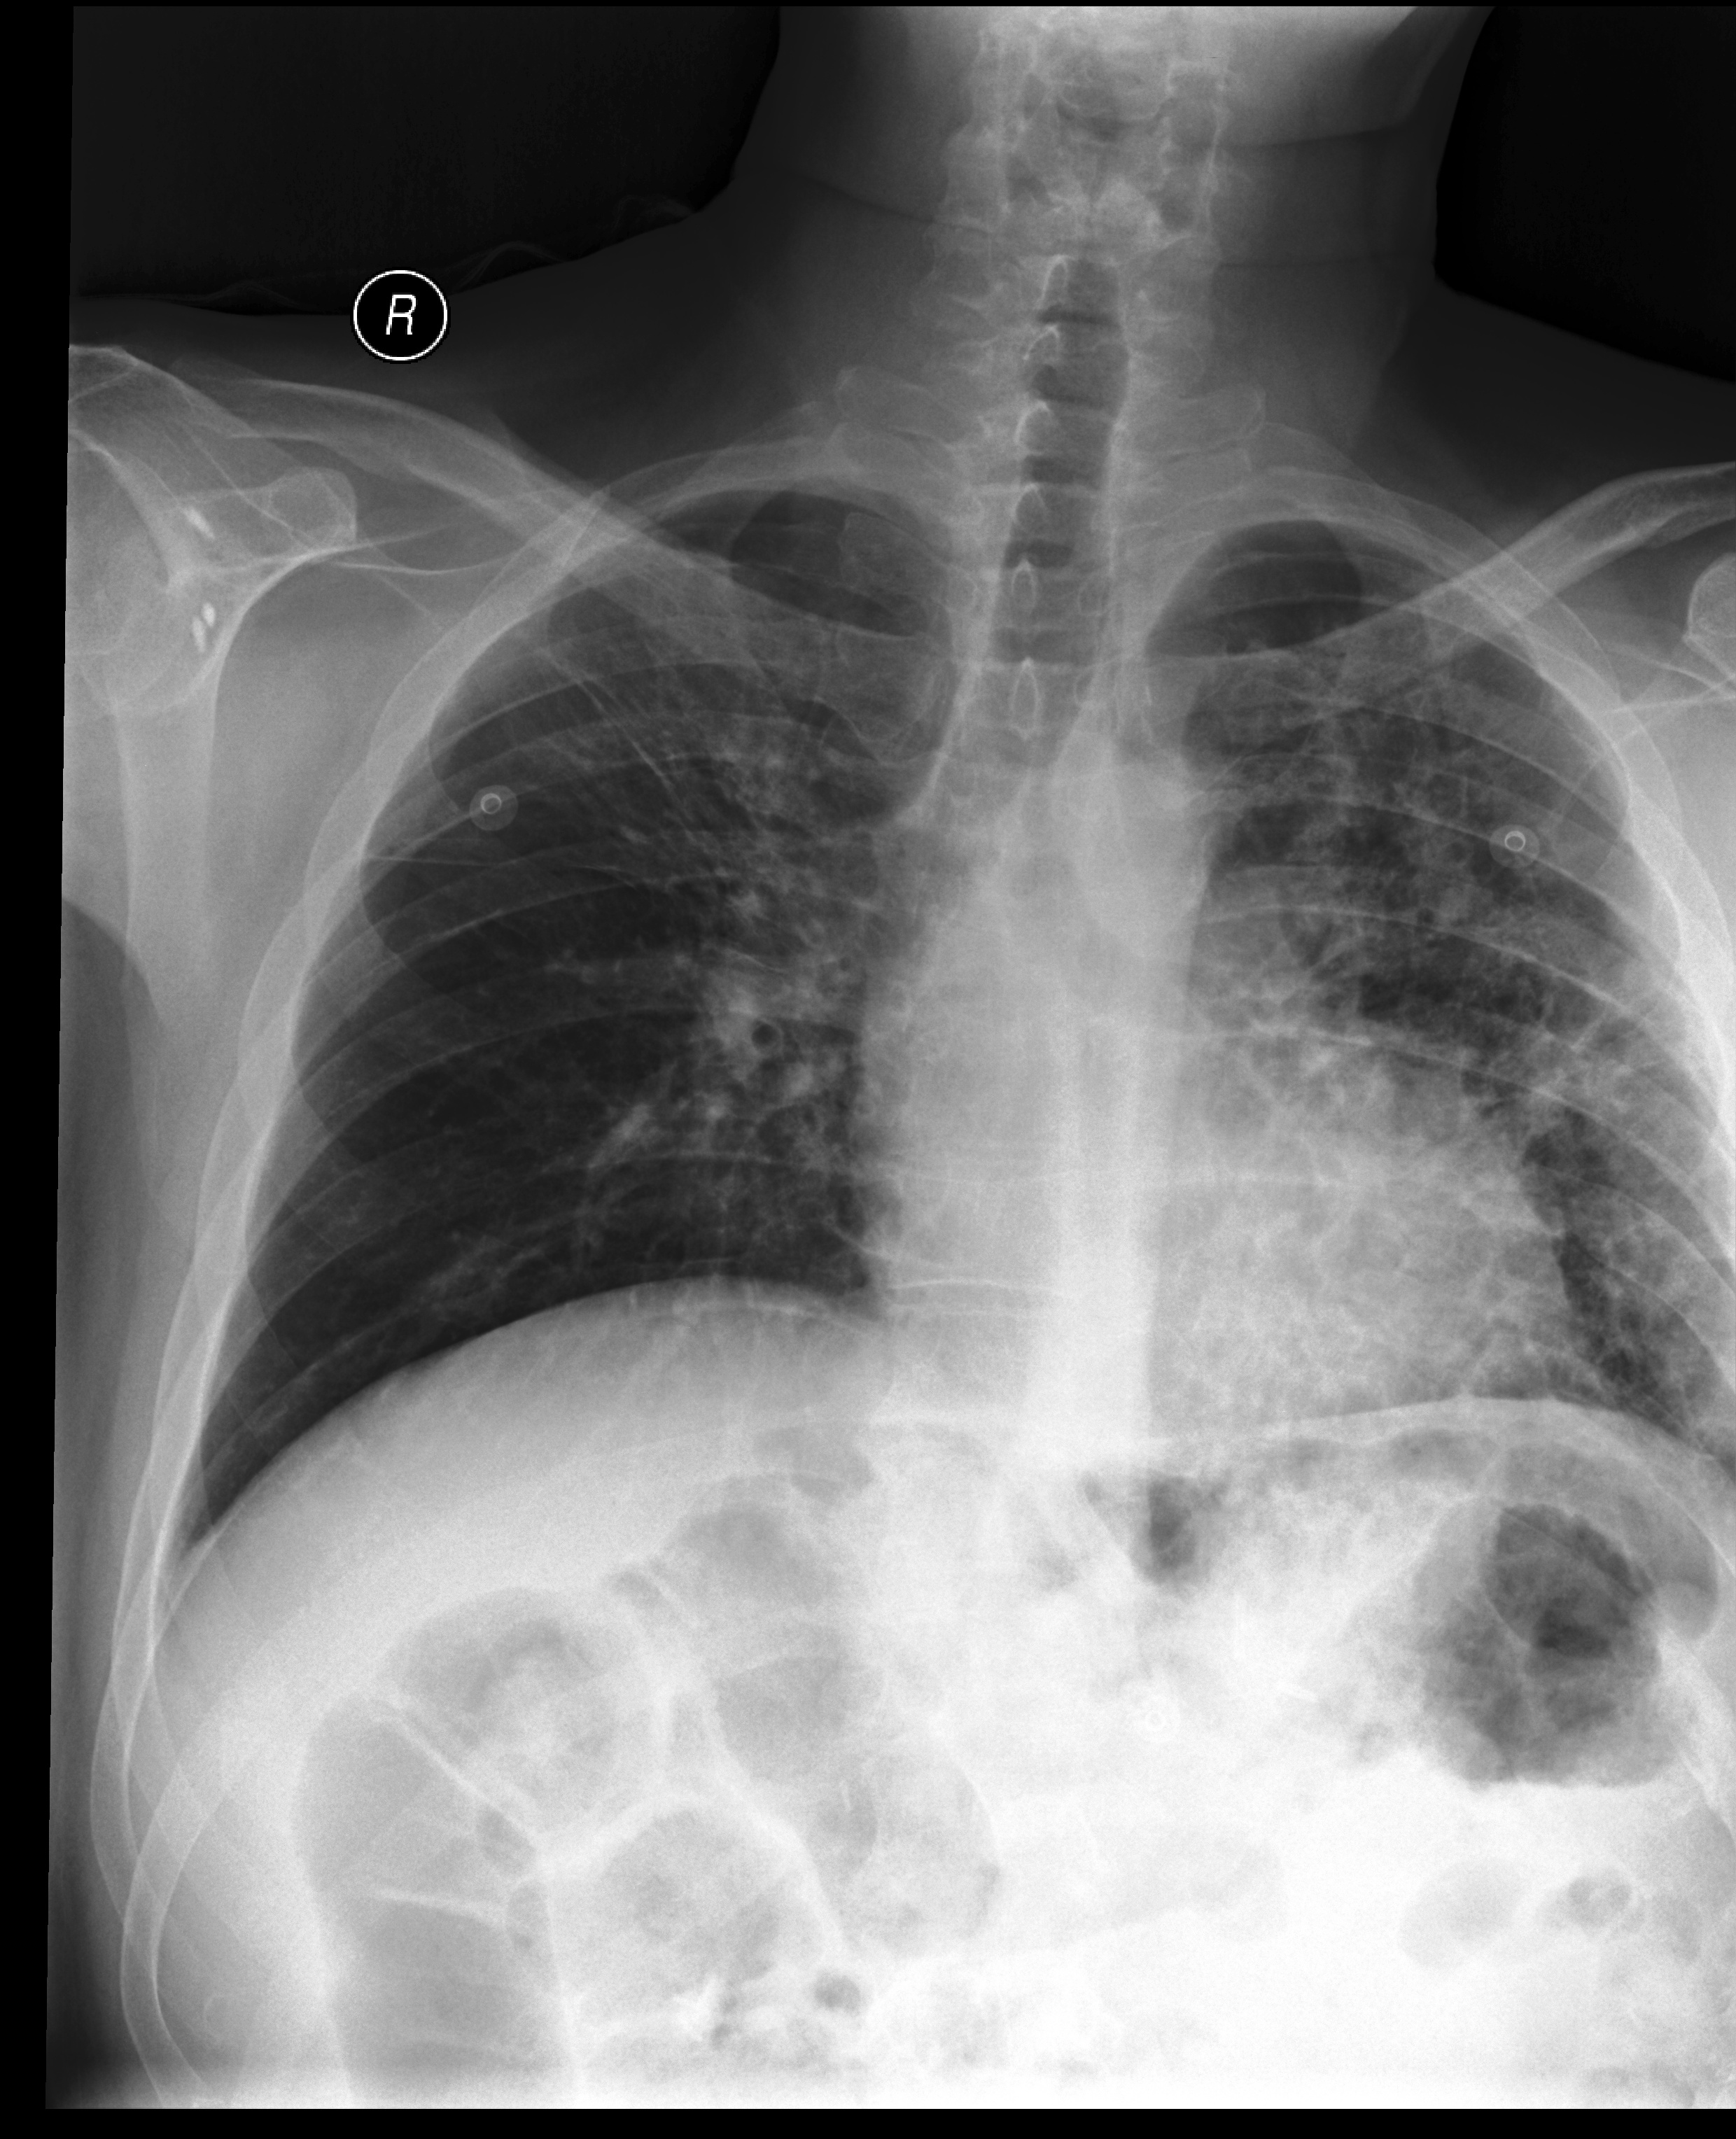

Example 3

[Uncaptioned image]

Generated

レントゲン写真を読影した結果、左肺下葉に不規則な影が見られます。心臓の形状は正常です。骨には異常は見られません。左肺下葉の影は肺炎や肺癌などの可能性があります。詳細な検査が必要です。

(The X-ray examination shows an irregular opacity in the left lower lobe. The shape of the heart is normal, and no abnormalities are observed in the bones. The opacity in the left lower lobe may suggest possibilities such as pneumonia or lung cancer. Further detailed examination is required.)

Ground truth

ポータブル撮影画像。左肺下部の病変が拡大しており、胸水と浸潤影を疑う。肺野に散在する結節影は悪性腫瘍の転移を疑う。心陰影は不明瞭で心拡大の評価は困難。骨病変は指摘できず。

(Portable imaging shows an enlarged lesion in the lower left lung, raising suspicion of pleural effusion and infiltrates. Scattered nodules in the lung fields suggest possible metastasis of a malignant tumor. The cardiac silhouette is unclear, making it difficult to assess for cardiomegaly. No bone lesions are noted.)